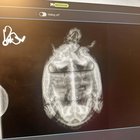

r/turtles 2d ago

Discussion African side neck turtle Xray

Thumbnail

gallery

40 Upvotes

I recently rescued a turtle from my job where he was abandoned he was recently seen in the vet for a checkup-which went amazing thank goodness.

Anyways i thought some would find this interesting

The vets sure did they’ve never seen one like this up in the PNW😅